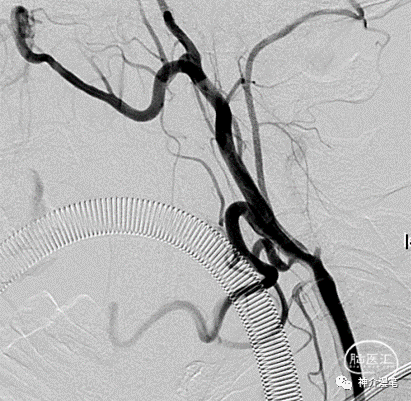

同样,从这个病例中我们仍然能看出支架放置后血管走行的趋势没有被过度的改变。但是下面这个病例,个人觉得支架种类的选择值得商榷。

这是一例颈内动脉起始处的溃疡性斑块,属于易损的不稳定斑块,术者在支架选择中选择了Protege支架,虽然影像效果尚满意,但是从支架种类的选择上讲,此血管走行并不迂曲,从斑块保护及局部修复的角度讲,是否Wallstent支架更为合适?当然任何事情都非绝对,更好的选择是否有可能带来更好的结果?

这个病例中,血管局部走行角度较大,wallsten植入后过多的改善了血管走行,让本来弯曲的血管变成一根直棍,一方面会增加局部血管的刺激造成再狭窄,另一方面血管皱褶的力度会向远端传导,造成远端血管走行变化甚至皱褶。这也是wallstent支架术后再狭窄率相对较高的重要原因,因此需要选择合适病例